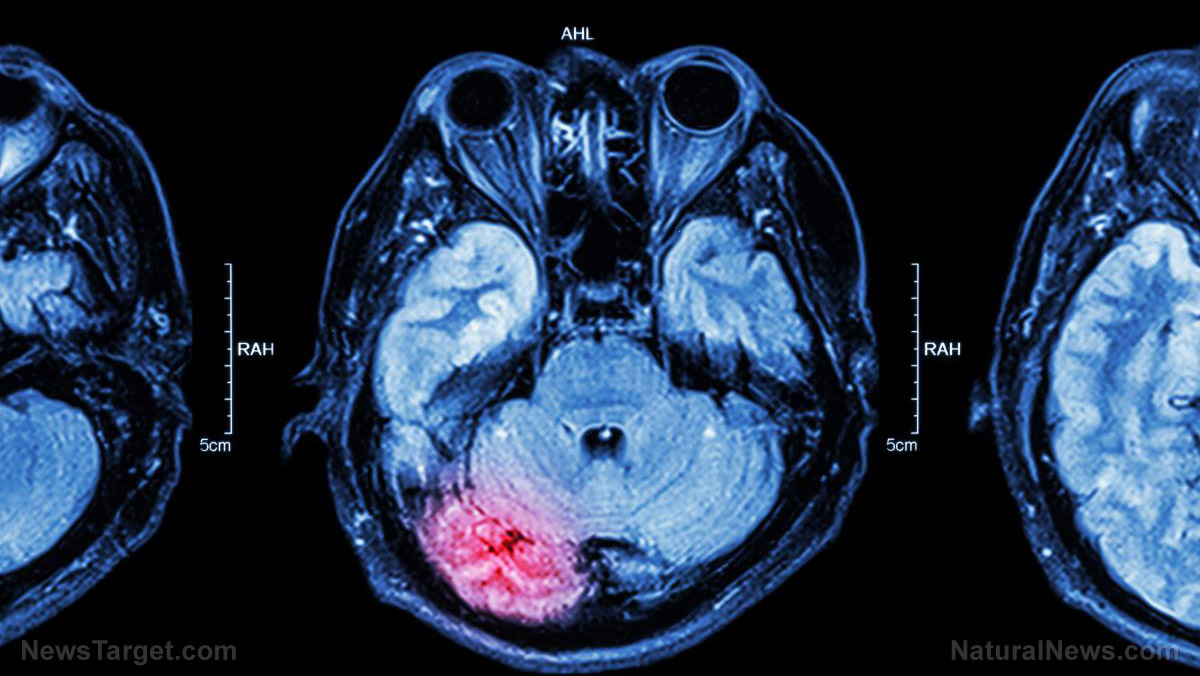

(Natural News) In any given year, about 25% of all U.S. adults have a mental illness and nearly 50% of U.S. adults will develop at least one mental illness during their lifetime. These statistics are staggering! Yet, when it comes to brain health and behavioral disorders, Western medicine is clearly missing the point – in… |